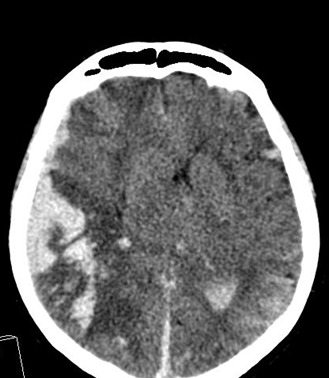

In acute phase (12-24 hours after the occlusion of the middle cerebral artery) on CT hypodense basal ganglia, the loss of cortical white-grey matter differentiation and sulcal effacement are the characteristic imaging findings.

On MRI, diffusion restriction causes hyperintense signal on T2W images. The leptomeningeal border of the infract zone will show contrast enhancement.

After 1-3 days the “mass-effect” of the infarct increases. It is more apparent in case of large territorial infarcts, the sulcal effacement completes, the loss of cortical white matter and grey matter differentiation is more pronounced (especially in the white matter) due to the increased hypodensity. Hemorrhagic transformation in the grey matter (cortex, basal ganglia) can also occur at this stage. It is worth to note, that for hemorrhagic transformation one should not always blame thrombolytic therapy; it rather occurs spontaneously in a great majority of the cases.